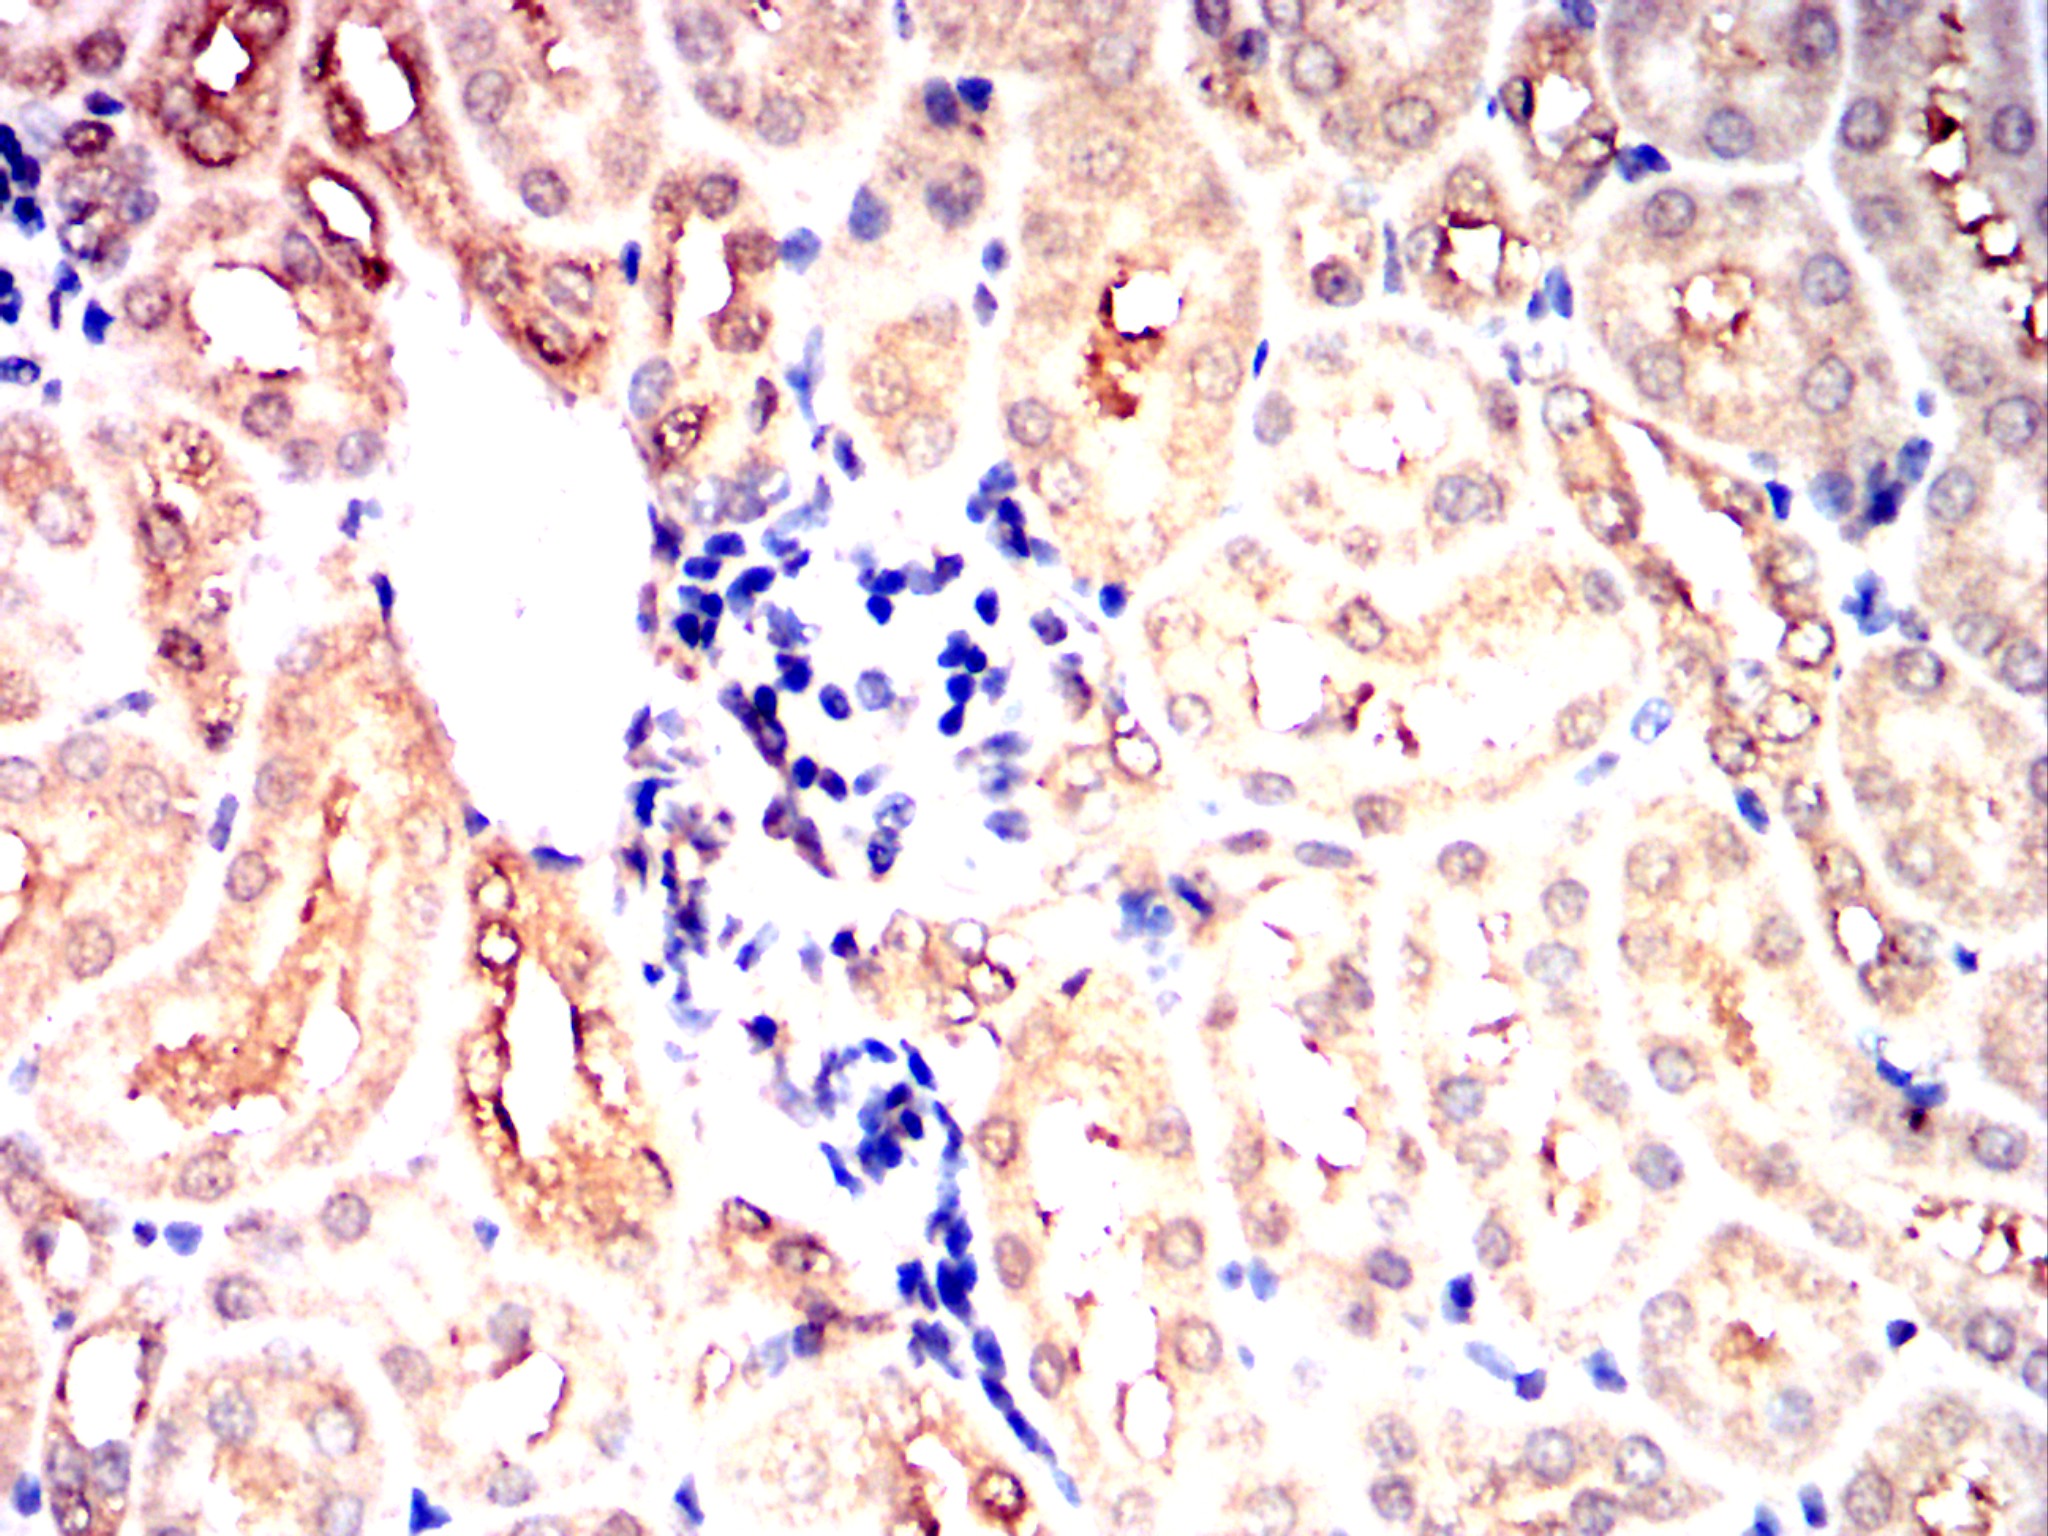

Immunohistochemical analysis of paraffin-embedded Mouse kidney using PRKAA2 mouse mAb with DAB staining.